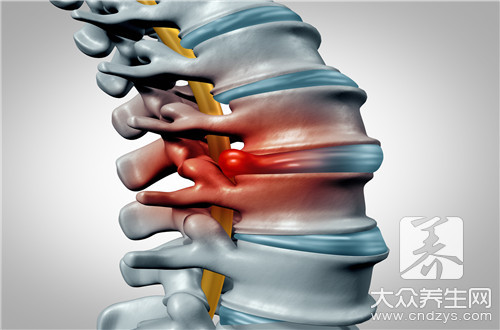

脊椎酸痛这样的现象几乎每一个人都体验过,特别是对于那些体力劳动者来说,在白天的时候,他们需要耗费大量的体力,搬抗一些重物这样是最容易造成脊柱损伤的,在第二天早上醒来就会出现脊椎酸痛,久而久之下去很可能就会造成脊椎炎,那么脊椎骨酸痛是怎么回事呢?

很多人出现脊椎骨疼都认为自己的是因为近太过于劳累导致的,其实有些人不是,有可能是因为患上某些疾病引起的,所以不要出现脊椎骨疼就单纯地认为是自己太累了导致的。

颈椎病引起的

如果您的颈椎出了问题的话,那肯定会导致您出现脊椎骨疼的,所以谨防颈椎病的出现,一旦发现了,就一定要及时调理,不然的话,只会加重您脊椎骨疼,让您的颈椎一天不如一天。

1、原因

(1)颈椎第四、五、六颈椎的脊神经后支向背部延伸,支配上背部的皮肤肌肉。(2)当颈椎发生退行性改变时,如果牵拉到第四、五、六颈椎的脊神经后支,就会导致出现背痛。2、症状表现

颈背疼痛、上肢无力、手指发麻,头晕、恶心甚至视物模糊,吞咽模糊都是颈椎病的症状表现。

颈部扭伤和落枕引起的

还有一个原因就是看看自己睡觉有没有落枕,或者因为其他的原因导致自己的颈部扭伤了,这两个也是会导致您的脊椎骨疼的,所以平时的睡眠要注意,枕头的高度也是要注意的。

1、原因

由于颈部活动不当,或睡眠体位不良导致局部肌肉被扭伤,伤痛牵扯背部肌肉,病史较短,压痛点固定且位于肌肉损伤部。

2、症状表现

以肩胛内上方多见,且伴肌肉痉挛,可触及压痛明显的条索状痉挛肌束,颈背部活动受限明显。